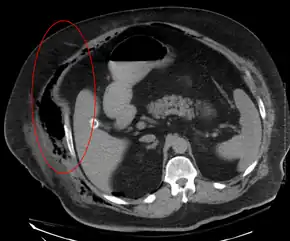

Necrotizing fasciitis producing gas in the soft tissues as seen on CT scan

Medical imaging

Imaging has a limited role in the diagnosis of necrotizing fasciitis. The time delay in performing imaging is a major concern. Plain radiography may show subcutaneous emphysema (gas in the subcutaneous tissue), which is strongly suggestive of necrotizing changes, but it is not sensitive enough to detect all the cases, because necrotizing skin infections caused by bacteria other than clostridial infections usually do not show subcutaneous emphysema. If the diagnosis is still in doubt, computed tomography (CT) scans and magnetic resonance imaging (MRI) are more sensitive modalities than plain radiography. However, both the CT scan and MRI are not sensitive enough to rule out necrotizing changes completely.[2] CT scan may show fascial thickening, edema, subcutaneous gas, and abscess formation.[2] In MRI, when fluid collection with deep fascia involvement occurs, thickening or enhancement with contrast injection, necrotizing fasciitis should be strongly suspected. Meanwhile, ultrasonography can show superficial abscess formation, but is not sensitive enough to diagnose necrotizing fasciitis.[2] CT scan is able to detect about 80% of cases, while MRI may pick up slightly more.[18]